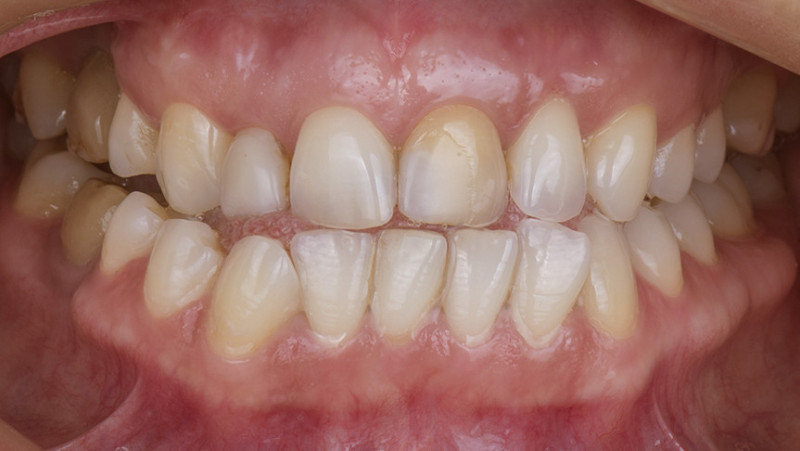

Установка керамической коронки

Изготовили и установили 22 керамические коронки EMAX и 6 виниров на нижнюю челюсть. Провели пластику десны в области 22 зуба. Устранили сильную рецессию десны в области имплантата, установленного в другой клинике.